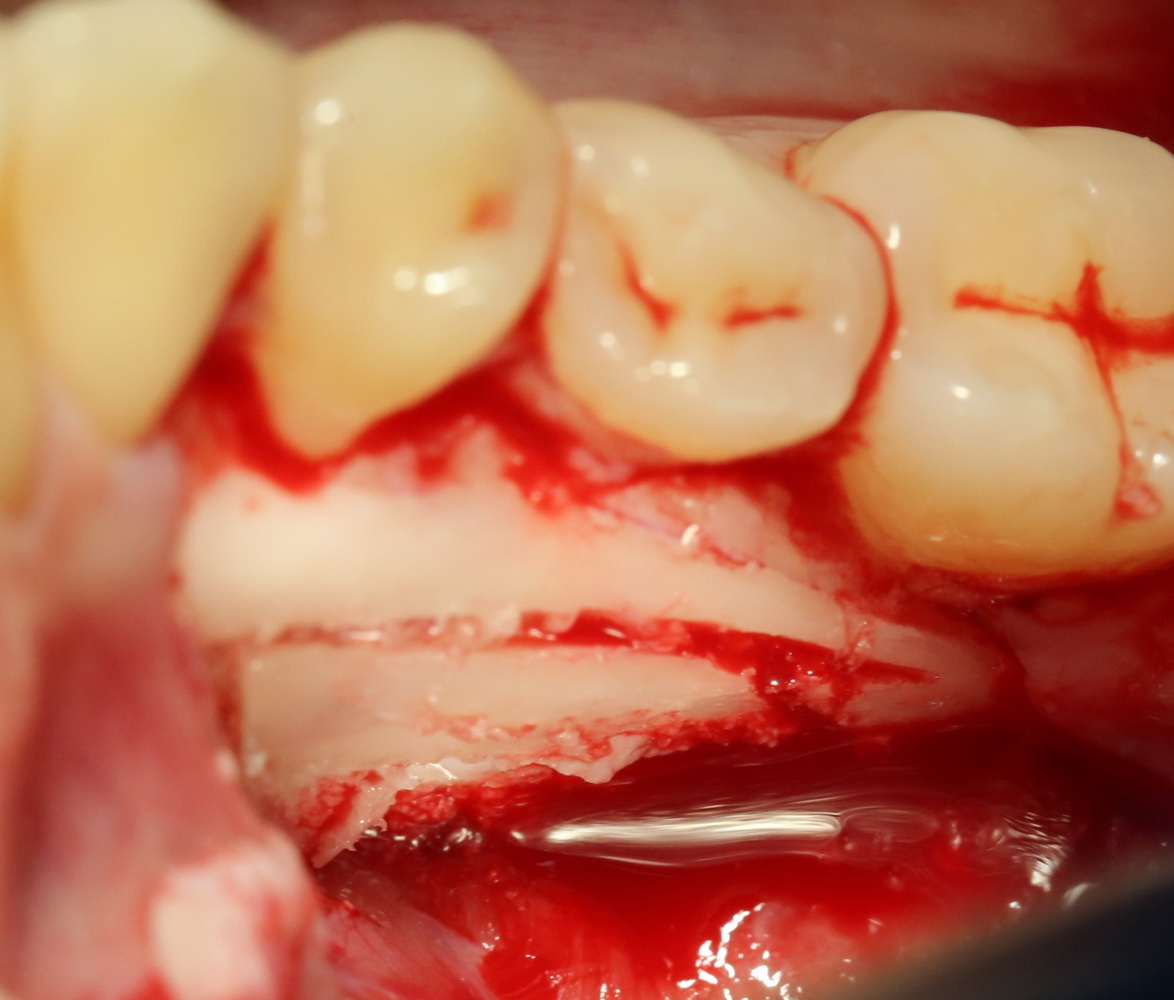

Итак, ультразвуковой разрез по костной ткани:

Костная «дверца» на время отделяется и убирается в физраствор, а мы видим следующее:

Это фолликулы и, частично, коронковые части сверхкомплектных зубов.

Теперь аккуратно нам нужно выделить сами зубы:

А вот они! Далее мы руководствуемся главным правилом хирурга-стоматолога:

Поэтому мы, всё также, с помощью ультразвука, отпиливаем коронку одного из зубов:

После чего, зубы вываливаются из лунок самостоятельно. В прямом смысле слова: